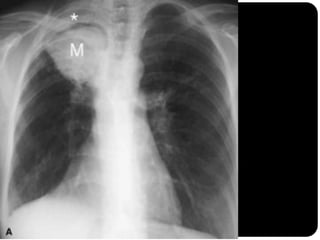

Nódulos pulmonares múltiplos Causas mais comum em adultos: neoplasia metastática (diversos diâmetros, densidade de tecido mole, raramente calcificada, exceto osteossarcoma) doença infecciosa (fúngicas e micobacterianas); nódulos acinares: pneumonias virais – herpes e catapora;

Carcinoma de tireóidecom metástases pulmonares;